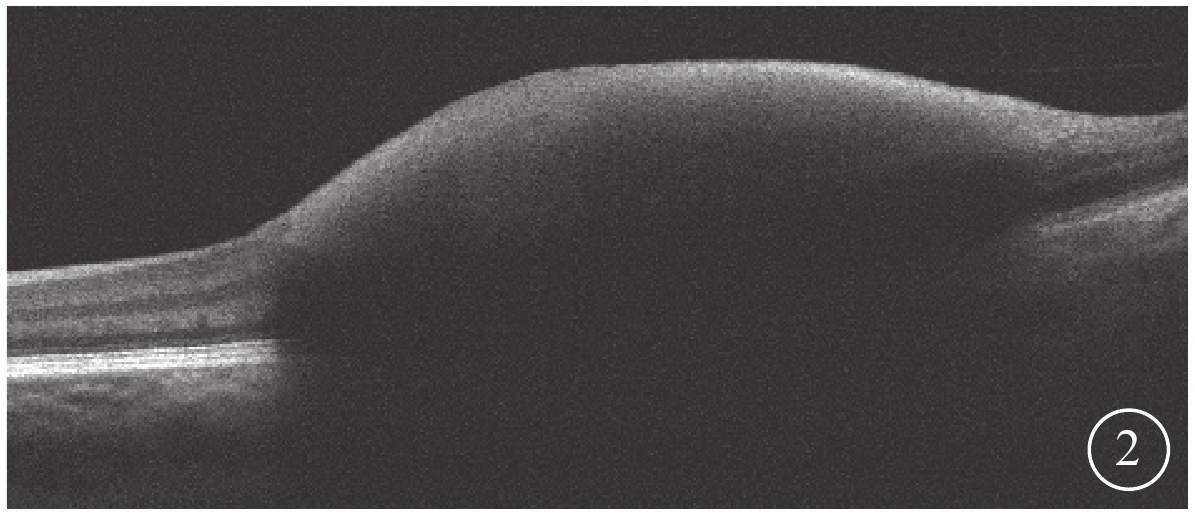

3只眼均行常規全身檢查及最佳矯正視力(BCVA)、眼壓、裂隙燈顯微鏡、眼底彩色照相、眼部B型超聲、熒光素眼底血管造影(FFA)及光相干斷層掃描(OCT)等眼部檢查。患眼BCVA為手動/20 cm~0.06,平均BCVA為0.03±0.02。眼壓為7.9~18.9 mmHg(1 mmHg=0.133 kPa),平均眼壓為(9.87±3.23)mmHg。3只眼均存在不同程度的晶狀體混濁。RAM位于視網膜顳上2只眼,位于視網膜顳下1只眼。黃斑區內界膜下出血大小為1.5~8.0倍視盤面積。FFA檢查發現,動脈期患眼顳下視網膜動脈分支處強熒光點,周圍出血遮蔽視網膜及脈絡膜熒光(圖1)。OCT檢查發現,患眼出血灶表面可見一弧形強反射條帶,且與內界膜相對應,其下呈點狀強反射(圖2)。

圖2

圖1同眼OCT像。黃斑視網膜內層強反射

圖2

圖1同眼OCT像。黃斑視網膜內層強反射

3只患眼經FFA檢查均可見動脈期顳側視網膜動脈分支處強熒光點,周圍出血遮蔽視網膜及脈絡膜熒光;OCT檢查可見出血灶表面一弧形強反射條帶,且與內界膜相對應,其下呈點狀強反射。證明其RAM及內界膜下出血診斷成立[5]。

3只眼均行常規全身檢查及最佳矯正視力(BCVA)、眼壓、裂隙燈顯微鏡、眼底彩色照相、眼部B型超聲、熒光素眼底血管造影(FFA)及光相干斷層掃描(OCT)等眼部檢查。患眼BCVA為手動/20 cm~0.06,平均BCVA為0.03±0.02。眼壓為7.9~18.9 mmHg(1 mmHg=0.133 kPa),平均眼壓為(9.87±3.23)mmHg。3只眼均存在不同程度的晶狀體混濁。RAM位于視網膜顳上2只眼,位于視網膜顳下1只眼。黃斑區內界膜下出血大小為1.5~8.0倍視盤面積。FFA檢查發現,動脈期患眼顳下視網膜動脈分支處強熒光點,周圍出血遮蔽視網膜及脈絡膜熒光(圖1)。OCT檢查發現,患眼出血灶表面可見一弧形強反射條帶,且與內界膜相對應,其下呈點狀強反射(圖2)。

圖2

圖1同眼OCT像。黃斑視網膜內層強反射

圖2

圖1同眼OCT像。黃斑視網膜內層強反射

3只患眼經FFA檢查均可見動脈期顳側視網膜動脈分支處強熒光點,周圍出血遮蔽視網膜及脈絡膜熒光;OCT檢查可見出血灶表面一弧形強反射條帶,且與內界膜相對應,其下呈點狀強反射。證明其RAM及內界膜下出血診斷成立[5]。